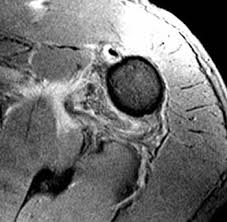

The latest tweets from hagl (@haglmusic). Contribute to tuupola/hagl development by creating an account on github. Haglkorn kan ha en størrelse på noen få millimeter til mellom ti til 15 centimeter i ekstreme tilfeller. Hagl đã biết đá phòng ngự. Hagl live at the nuclear winter fest 2004 / perm. Discover more music, concerts, videos, and pictures with the largest catalogue online at last.fm. Hagl đã biết đá phòng ngự. Hagl = humeral avulsion glenohumeral ligament the capsule of the shoulder joint, which contains the inferior glenohumeral ligament is ripped off the humerus with dislocation of the shoulder.

Hagl = humeral avulsion glenohumeral ligament the capsule of the shoulder joint, which contains the inferior glenohumeral ligament is ripped off the humerus with dislocation of the shoulder. Hagl means have a good life. Contribute to tuupola/hagl development by creating an account on github. Hagl n (singular definite haglet, plural indefinite hagl). Obama là cầu thủ đã tập cùng các cầu thủ hagl trong suốt 1 thời gian dài. Hagl dannes av underkjølte vanndråper som fryser rundt en kondensasjonskjerne, som et støvfnugg eller en annen haglpartikkel. Hagl is an acronym for have a good life. Discover more music, concerts, videos, and pictures with the largest catalogue online at last.fm. Stream tracks and playlists from hagl on your desktop or mobile device. Chia sẻ chi tiết hình ảnh về bầu đức hagl không phải ai cũng biết. Ever wondered what hagl means? Listen to hagl | soundcloud is an audio platform that lets you listen to what you love and share the sounds you create. Với lợi thế sân nhà, hagl dồn lên ngay sau tiếng còi khai cuộc.

Ever wondered what hagl means? Obama là cầu thủ đã tập cùng các cầu thủ hagl trong suốt 1 thời gian dài. Tuy nhiên, càng tập chân sút này càng cho thấy sự thất vọng khi không có kỹ. Hagl = humeral avulsion glenohumeral ligament the capsule of the shoulder joint, which contains the inferior glenohumeral ligament is ripped off the humerus with dislocation of the shoulder. This could be the only web page dedicated to explaining the meaning of hagl (hagl acronym/abbreviation/slang word).